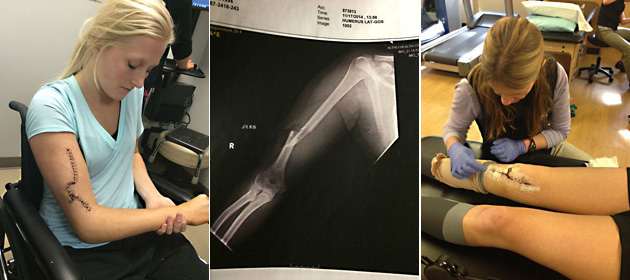

Lisa's right arm had been crushed and broken in three spots. The humerus bone was missing a three-inch chunk. It had splintered and punctured the skin, creating a hole the size of a large bottle cap. Her right knee had been destroyed, its anterior cruciate, medial collateral and posterior cruciate ligaments torn, the oblique lateral and meniscus also damaged.

Then there was the nerve damage. When her humerus shot through her arm, it stretched Lisa's radial and ulnar nerves, more or less paralyzing her right wrist and hand. "It was stuck in a fist," she says. "I literally just physically could not open it.”

By the end of the third month after the accident, Lisa was on her way to becoming independent again. She had perfected using her left arm to wheel herself to the kitchen sink and she used the counter to pull herself up to a standing position on her left leg so she could brush her teeth. Around the same time, she started transitioning from her wheelchair to a walker before trading the walker for a cane. Her right arm slowly started to come back to life after months of therapy and eight different braces. Shoulder mobility was the first part to return to normal. Range of motion in her elbow was next. Nerve growth, though, was another issue.